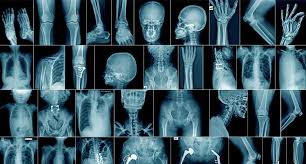

Radiology services

Radiology Service is one of Medical and Allied Health Sciences (MAHS) services and designed for executing general radiography and ultra sound exams and send back results.